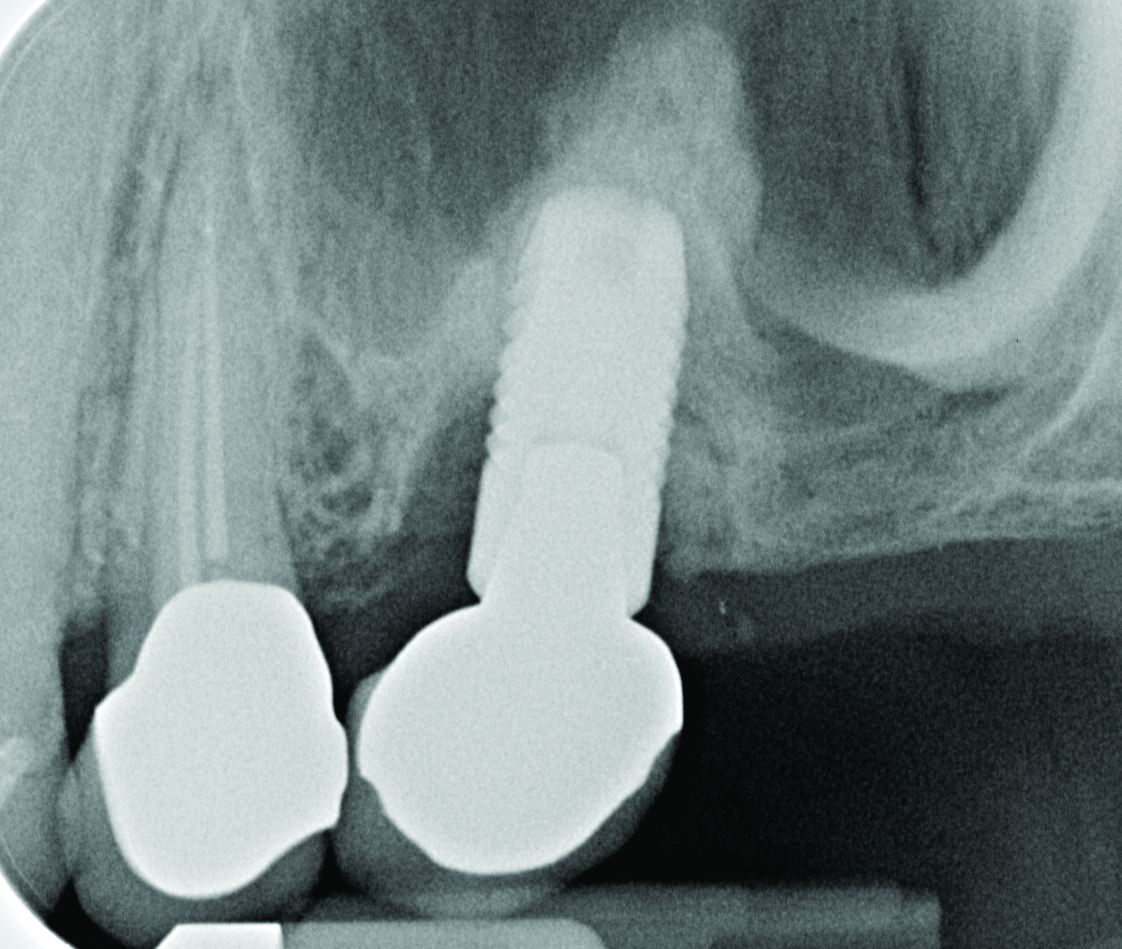

Clinical view of maxillary left lateral incisor implant in a healthy 48-year-old man. The swelling in the tissue surrounding this implant also bled on probing with depths up to 8 mm and exhibited purulence. The implant has been present for 14 years.

Figure 1

Radiograph of this same area. Note that there is no indication of bone loss and a long abutment collar. Hence, the diagnosis of peri-implant mucositis is given.

Figure 2